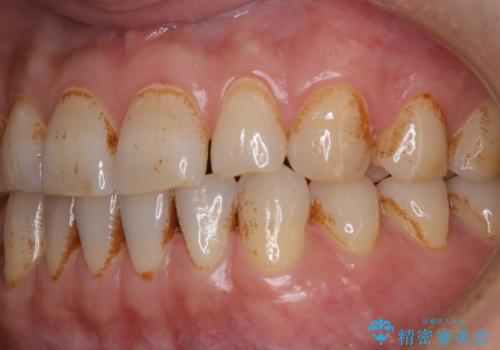

タバコとコーヒーによる頑固な着色落とし

- 毎日の喫煙とコーヒーを飲むことにより、ひどく着色がついてしまったとのことです。PMTC60分コースを行いました。